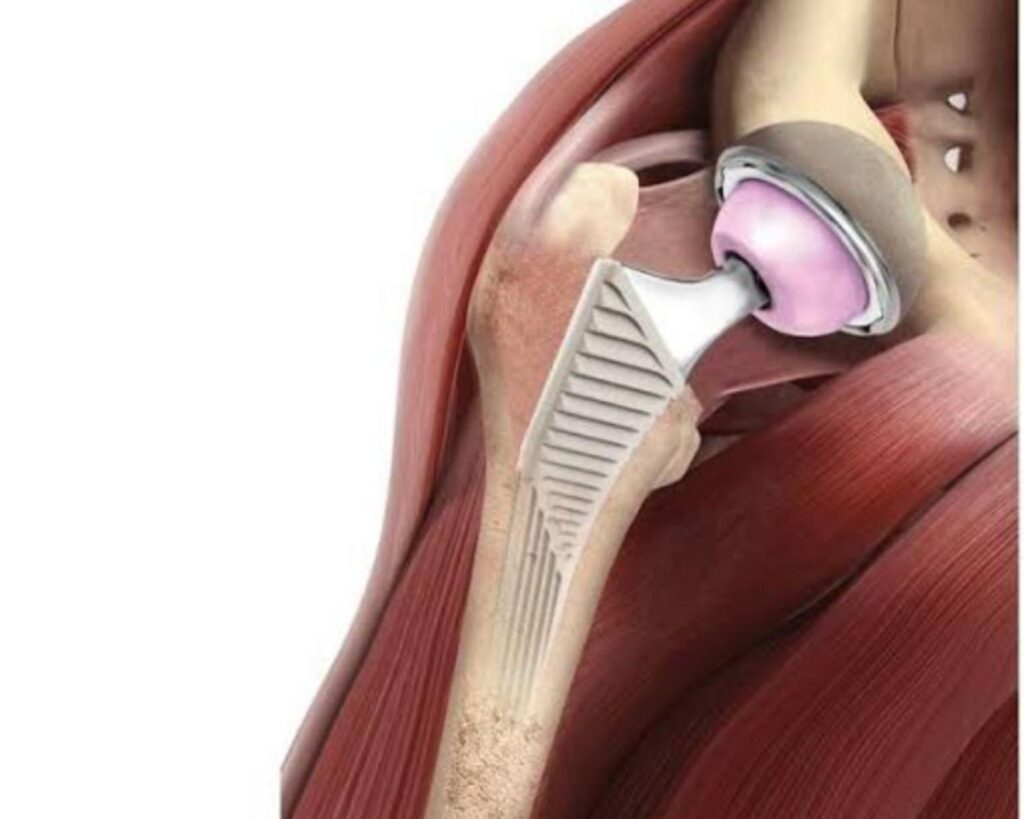

A cirurgia de prótese total de quadril já é consagrada na ortopedia, devido aos seus excelentes resultados e ao alto nível de satisfação dos pacientes submetidos. A novidade desta nova maneira de realizar a cirurgia é que a abordagem é pela via anterior do quadril e, como consequência, tem um pós-operatório para o paciente muito mais tranquilo. Normalmente, a pessoa já caminha com auxílio das muletas no mesmo dia do procedimento, e a alta hospitalar acontece no dia seguinte. A indicação da prótese por via anterior é exclusivamente do profissional médico ortopedista, que avalia individualmente cada paciente com indicação de prótese de quadril

Ainda de acordo com o médico ortopedista, a técnica utilizada é minimamente invasiva, pois a forma de acesso à articulação do quadril permite a implantação da prótese sem cortes nos músculos e nos tendões. “O paciente que se submete ao procedimento tem uma reabilitação mais rápida, com menos dor e menor risco de luxação, ou deslocamento da prótese”, afirmou.

A prótese de quadril é indicada para os pacientes que têm doenças que deterioram progressivamente essa articulação, como a artrose ou necrose (morte das células ou tecidos no organismo) da cabeça femoral. Além disso, ela auxilia o tratamento de algumas fraturas do fêmur ou, mais raramente, no acetábulo (a cavidade da articulação do quadril).

Imagem ilustrativa da prótese